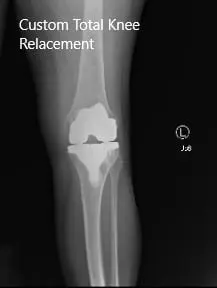

Post-Operative X-ray images showing AP and Lateral view:

The patient had an excellent recovery post arthroplasty. Her surgical wound was clean, dry and intact. The patient underwent an extensive program of physical therapy and a home exercise program.

During subsequent visits, she demonstrated a full range of motion with no pain. She stated she is now able to carry her daily activities without pain. She has since returned to work stating that she feels more motivated towards her work.